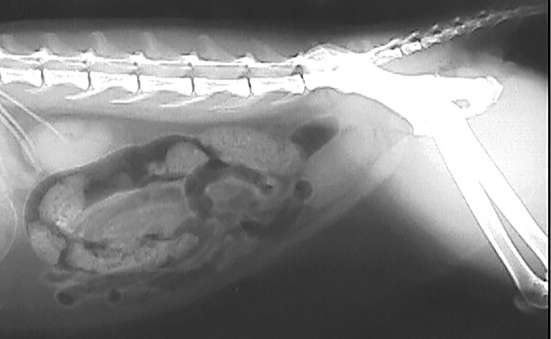

Inflammation is one of the most common issues. Networking with other incontinent cat caregivers can be very helpful. Bladder cancer in cats and dogs usually is transitional cell carcinoma, which arises from the epithelial cells that line the bladder.

Lack of bladder control, also known as urinary incontinence, is a condition that most commonly affects spayed female larger breeds of dogs, and dogs who are middle aged to elderly. This can include urine dribbling without the. Symptoms of incontinence in cats. Lack of bladder control, also known as urinary incontinence, is a condition that most commonly affects spayed female larger breeds of dogs, and dogs who are middle aged to elderly.